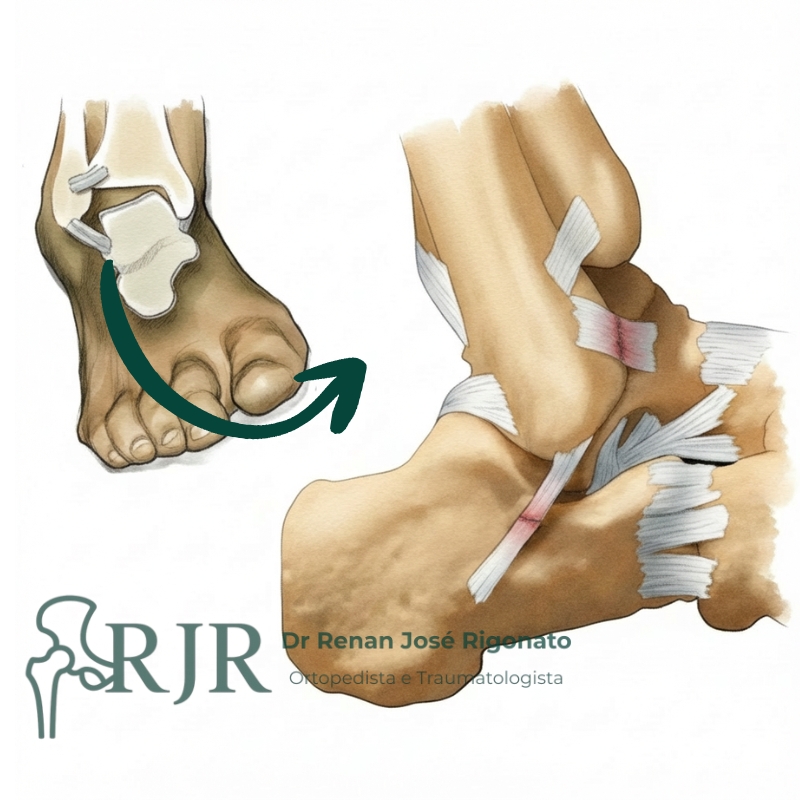

Lesões ligamentares

Os ligamentos são estruturas fundamentais para a estabilidade das articulações. Quando lesionados, podem causar dor, inchaço e insegurança ao movimentar. O diagnóstico preciso e o tratamento adequado ajudam a restaurar a função e prevenir novas lesões

Entorses